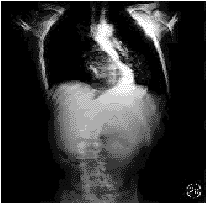

本组特发性脊柱侧凸患者占总病例数的74.7%(464/621),与文献报道的75%~80%相一致。但如果单独分析9~28岁常见手术年龄组的脊柱侧凸病例,则发现非特发性脊柱侧凸的构成百分比明显上升,由总病例数的25.3%(157/621)上升至34.0%(133/391)。表明在9~28岁这一常见手术年龄组内,有1/3的脊柱侧凸患者为非特发性脊柱侧凸。目前,国内外尚未见关于这一年龄组脊柱侧凸病因构成百分比的报道。史亚民等[14]和吴之康等[15]分别报告了177例和218例进行手术矫治的脊柱侧凸病例,其中非特发性脊柱侧凸者分别占30%和34%,说明在需要接受手术矫治的脊柱侧凸患者中约有1/3为非特发性脊柱侧凸者。本组非特发性脊柱侧凸构成百分比较高,可能与以下因素有关:(1)详细的全身体检发现了隐匿的神经系统体征,提示为非特发性脊柱侧凸。本组有2例腹壁反射减弱,3例有未曾引起注意的浅感觉减退而无任何其他神经系统的症状与体征,原诊断为特发性脊柱侧凸,经MRI检查发现有Chiari畸形和脊髓空洞(图1)。(2)对脊柱侧凸X线片特征的认识提高。我们经过X线片及体检筛选后,对胸椎“特发性”左侧凸或胸椎后突性侧凸病例进行MRI检查,发现部分患者合并有脊髓空洞或脊髓发育性畸形(图2)。(3)对脊柱侧凸发病原因和自然转归的认识加深。如对成年后侧凸仍明显加重或伴关节松弛、肝、脾肿大的脊柱侧凸患者,经进一步检查,确诊为神经肌源性脊柱侧凸(图3)和粘多糖病源性脊柱侧凸。

图2患者男,27岁2aX线正位片示胸椎侧凸除凸向左侧外,呈“典型”特发性脊柱侧凸表现2bMRI示颈髓空洞